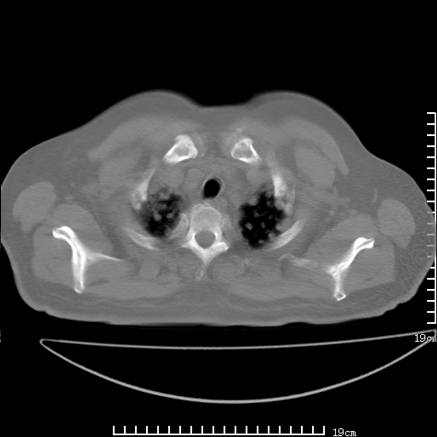

张男,75岁,干咳半年余,小便不利二年,b超检查前列腺增大,未见明显肿块;前列腺癌血生化检查多项指标明显增高。

双肺内多发转移瘤,纵膈淋巴结转移。来源前列腺?建议盆腔mri进一步检查。

双肺转移满了。

两肺广泛转移瘤。